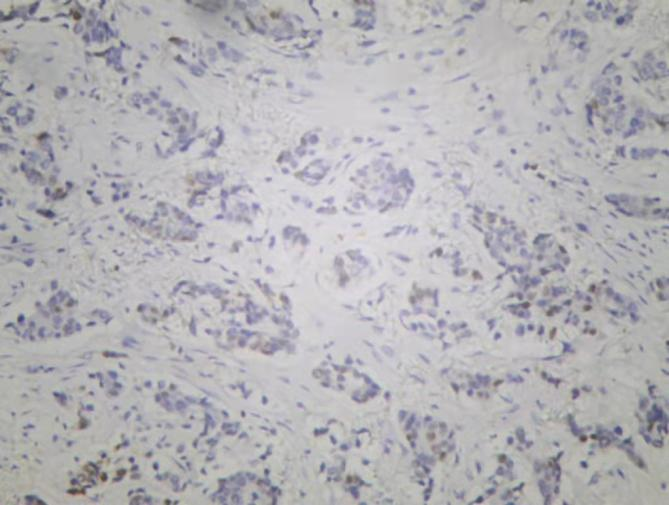

图3. 免疫组化Cerb-B2

图4. 免疫组化PR

图5. 免疫组化ER

图6. 免疫组化Ki-67